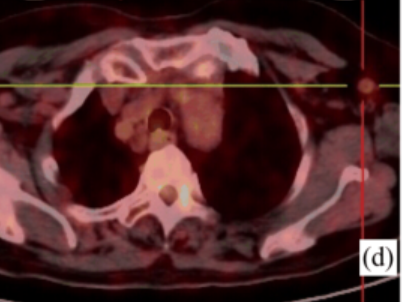

此前一位40岁的女性患者赵某某,因“发热伴皮疹1月”收入我院,患者曾于外院抗感染治疗无效,入我院后完善血常规:白细胞18.0×109/L,中性粒细胞百分比89.5%;铁蛋白4400ng/ml;血沉83mm/h;PCT0.10ng/ml;CRP82mg/L;抗核抗体谱、类风湿因子、抗“O”、肿瘤标志物、结核抗体、T-SPOT、血培养、腹部彩超等均未见异常,胸部CT提示肺部纤维灶,进一步完善骨髓穿刺、骨髓活检亦无明显异常,为明确患者发热伴皮疹原因,进一步行PET/CT检查,结果提示双侧腋窝、右侧髂外血管旁及双侧腹股沟区多发肿大淋巴结,局部淋巴结病灶FDG代谢轻度增高,考虑非特异性炎性改变。综合结合患者相关表现、检查以及排除其他病因,相关学科讨论后,初步考虑为成人still病,予以糖皮质激素治疗后皮疹消退、体温降至正常,病情平稳后带药出院。

图为患者赵女士的PET/CT融合成像显示腋窝、腹股沟淋巴结FDG摄取增高